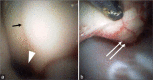

Methods: We report the use of an angioscope that is 1.8 mm in diameter and has both a thin and flexible tip. In this study, the angioscope was inserted into the lumen of an aspirator tube, and the tip of the device was placed at the intracranial area of intended observation area. Image findings were evaluated using an established in vivo goat brain model.

Results: The angioscope was light in weight and maneuverable and could be reached and observed in the blind spot using a surgical microscope. From the cerebellopontine angle, the lower cranial nerves and trigeminal nerve could be observed, and from the cisterna magna, the floor of the fourth ventricle and the aqueduct could be seen.